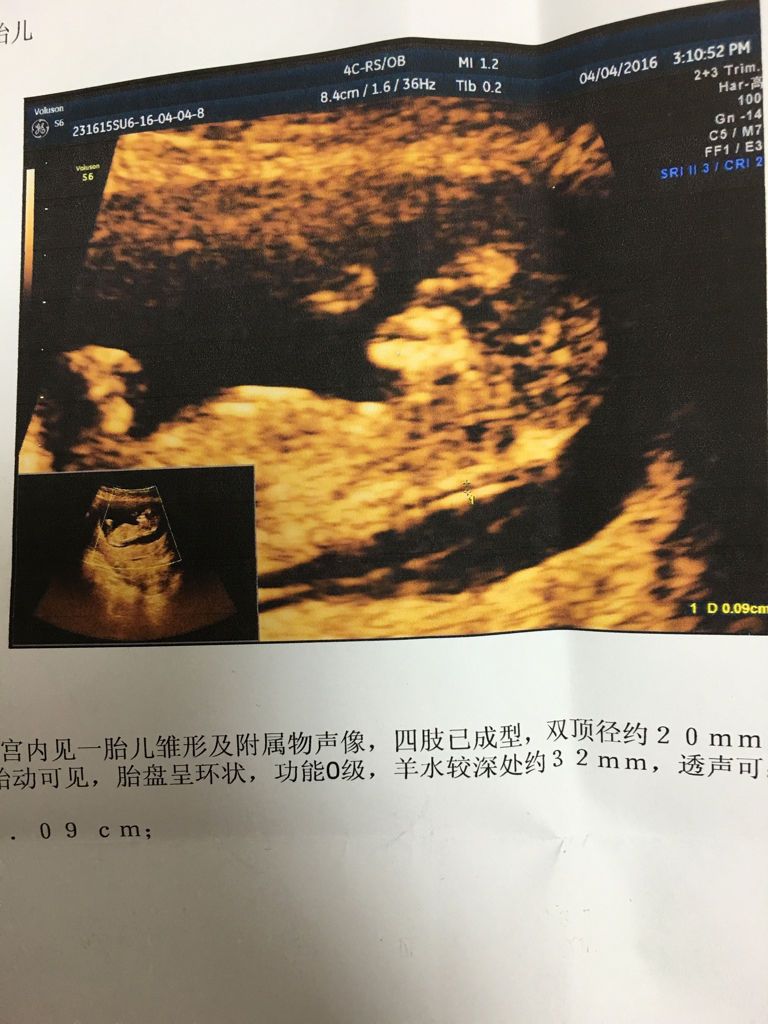

请问谁能看出宝宝是男是女,因为专家说胎教可以叫孩子昵称和ta交流,可是我男女各起了一个小名,我不想 请问谁能看出宝宝是男是女,因为专家说胎教可以叫孩子昵称和ta交流,可是我男女各起了一个小名,我不想用B超的方式看,听别人说要看很久才看得出,有时候因为四肢遮挡,要看很多次!这样太伤害ta了! 点击展开 匿名用户 2016-04-21 21:43 推荐回答 宝妈是在悬赏吗?哈哈,我觉得男宝女宝都可以只要健康就行。 弄墨倾城寒 2016-04-24 17:14 宝宝知道提示您:回答为网友贡献,仅供参考。 为您推荐: 其他回答 男的 匿名用户 2016-04-21 21:46 500块钱告诉你 母婴用户338968068 2016-04-21 21:45 女孩 匿名用户 2016-04-21 21:45 相关问题 有人看得懂这个单子么?想知道会是男孩还是女孩 想给他(她)取个小名了,想胎教的时候叫着他(她)的名字,会不会更有感觉啊? 大家给我家宝宝想个好听个性点的小名,我要给他胎教 亲们,胎教时如何和双胎宝宝打招呼,除了喊大宝小宝,还有其他好听的小名吗?